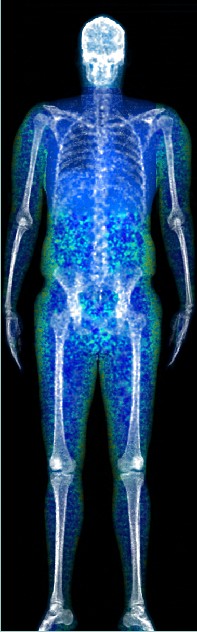

DEXA scans, what is the benefit of getting more than one scan?

All of our clients at Body Measure know that DEXA scans are the gold standard for body composition. The most …

ACHIEVING RESULTS THROUGH DEXA

ACHIEVING RESULTS THROUGH DEXA. Congrats to Pretty P, Body Measure’s client of the month for November! She has achieve great …

Not happy with your DEXA scan results? It’s not personal

We’ll be upfront. Having a DEXA scan can sometimes be a bit confronting. Knowing EXACTLY how much fat is on …